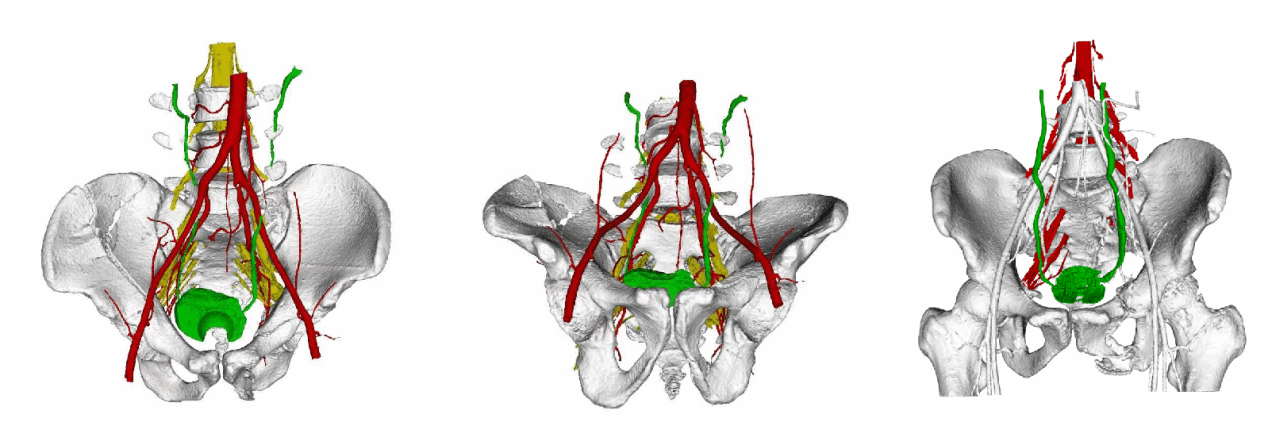

重大临床医疗成果(特等奖)——骨盆髋臼骨折精准微创诊疗体系的创建与推广应用

首席专家:创伤骨科负责人 樊仕才

项目简介:本项目构建了涵盖诊断、治疗与手术入路的全程微创诊疗体系。创新提出“骨盆骨折合并腰骶丛神经损伤”诊治理念,开发三维图像融合技术,并发明“个体化定制髋臼解剖接骨板”。团队研发4种符合国人解剖的骨盆髋臼解剖钢板,首创“腹直肌外侧入路”“直接后方入路”等微创术式,将手术切口从20厘米以上缩短至8–10厘米,显著提升手术精准度与康复效率。